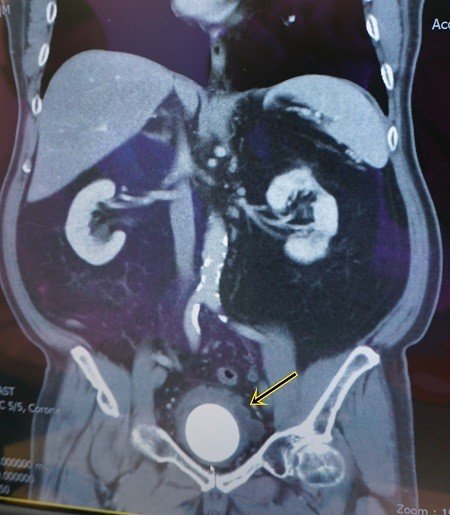

70歲陳姓男患者,在40歲後就出現了尿液混濁情形,但不以為意,隨著年紀增長而越來越頻尿,10年前還曾自行解出小石子,最近因為一個晚上都要起床如廁五、六次,且解尿時出現疼痛情形到童綜合醫院泌尿科求診。經泌尿科陳祥來醫師看診後進行尿流速檢查,發現患者最大尿流速每秒只有7毫升(正常值應該為每秒15毫升) ,再進行靜脈腎盂攝影術檢查後,確認陳先生罹患膀胱結石,且結石已有6公分大小,就像膀胱內部長了一顆奇異果大小的石頭。

因陳姓患者的結石已經太大,不適合使用內視鏡來手術,安排進行膀胱取石術,從下腹部切口進入膀胱取出結石,取出之石頭形狀與顏色如奇異果般,手術順利且排尿恢復正常,住院六天便可出院返家休養。